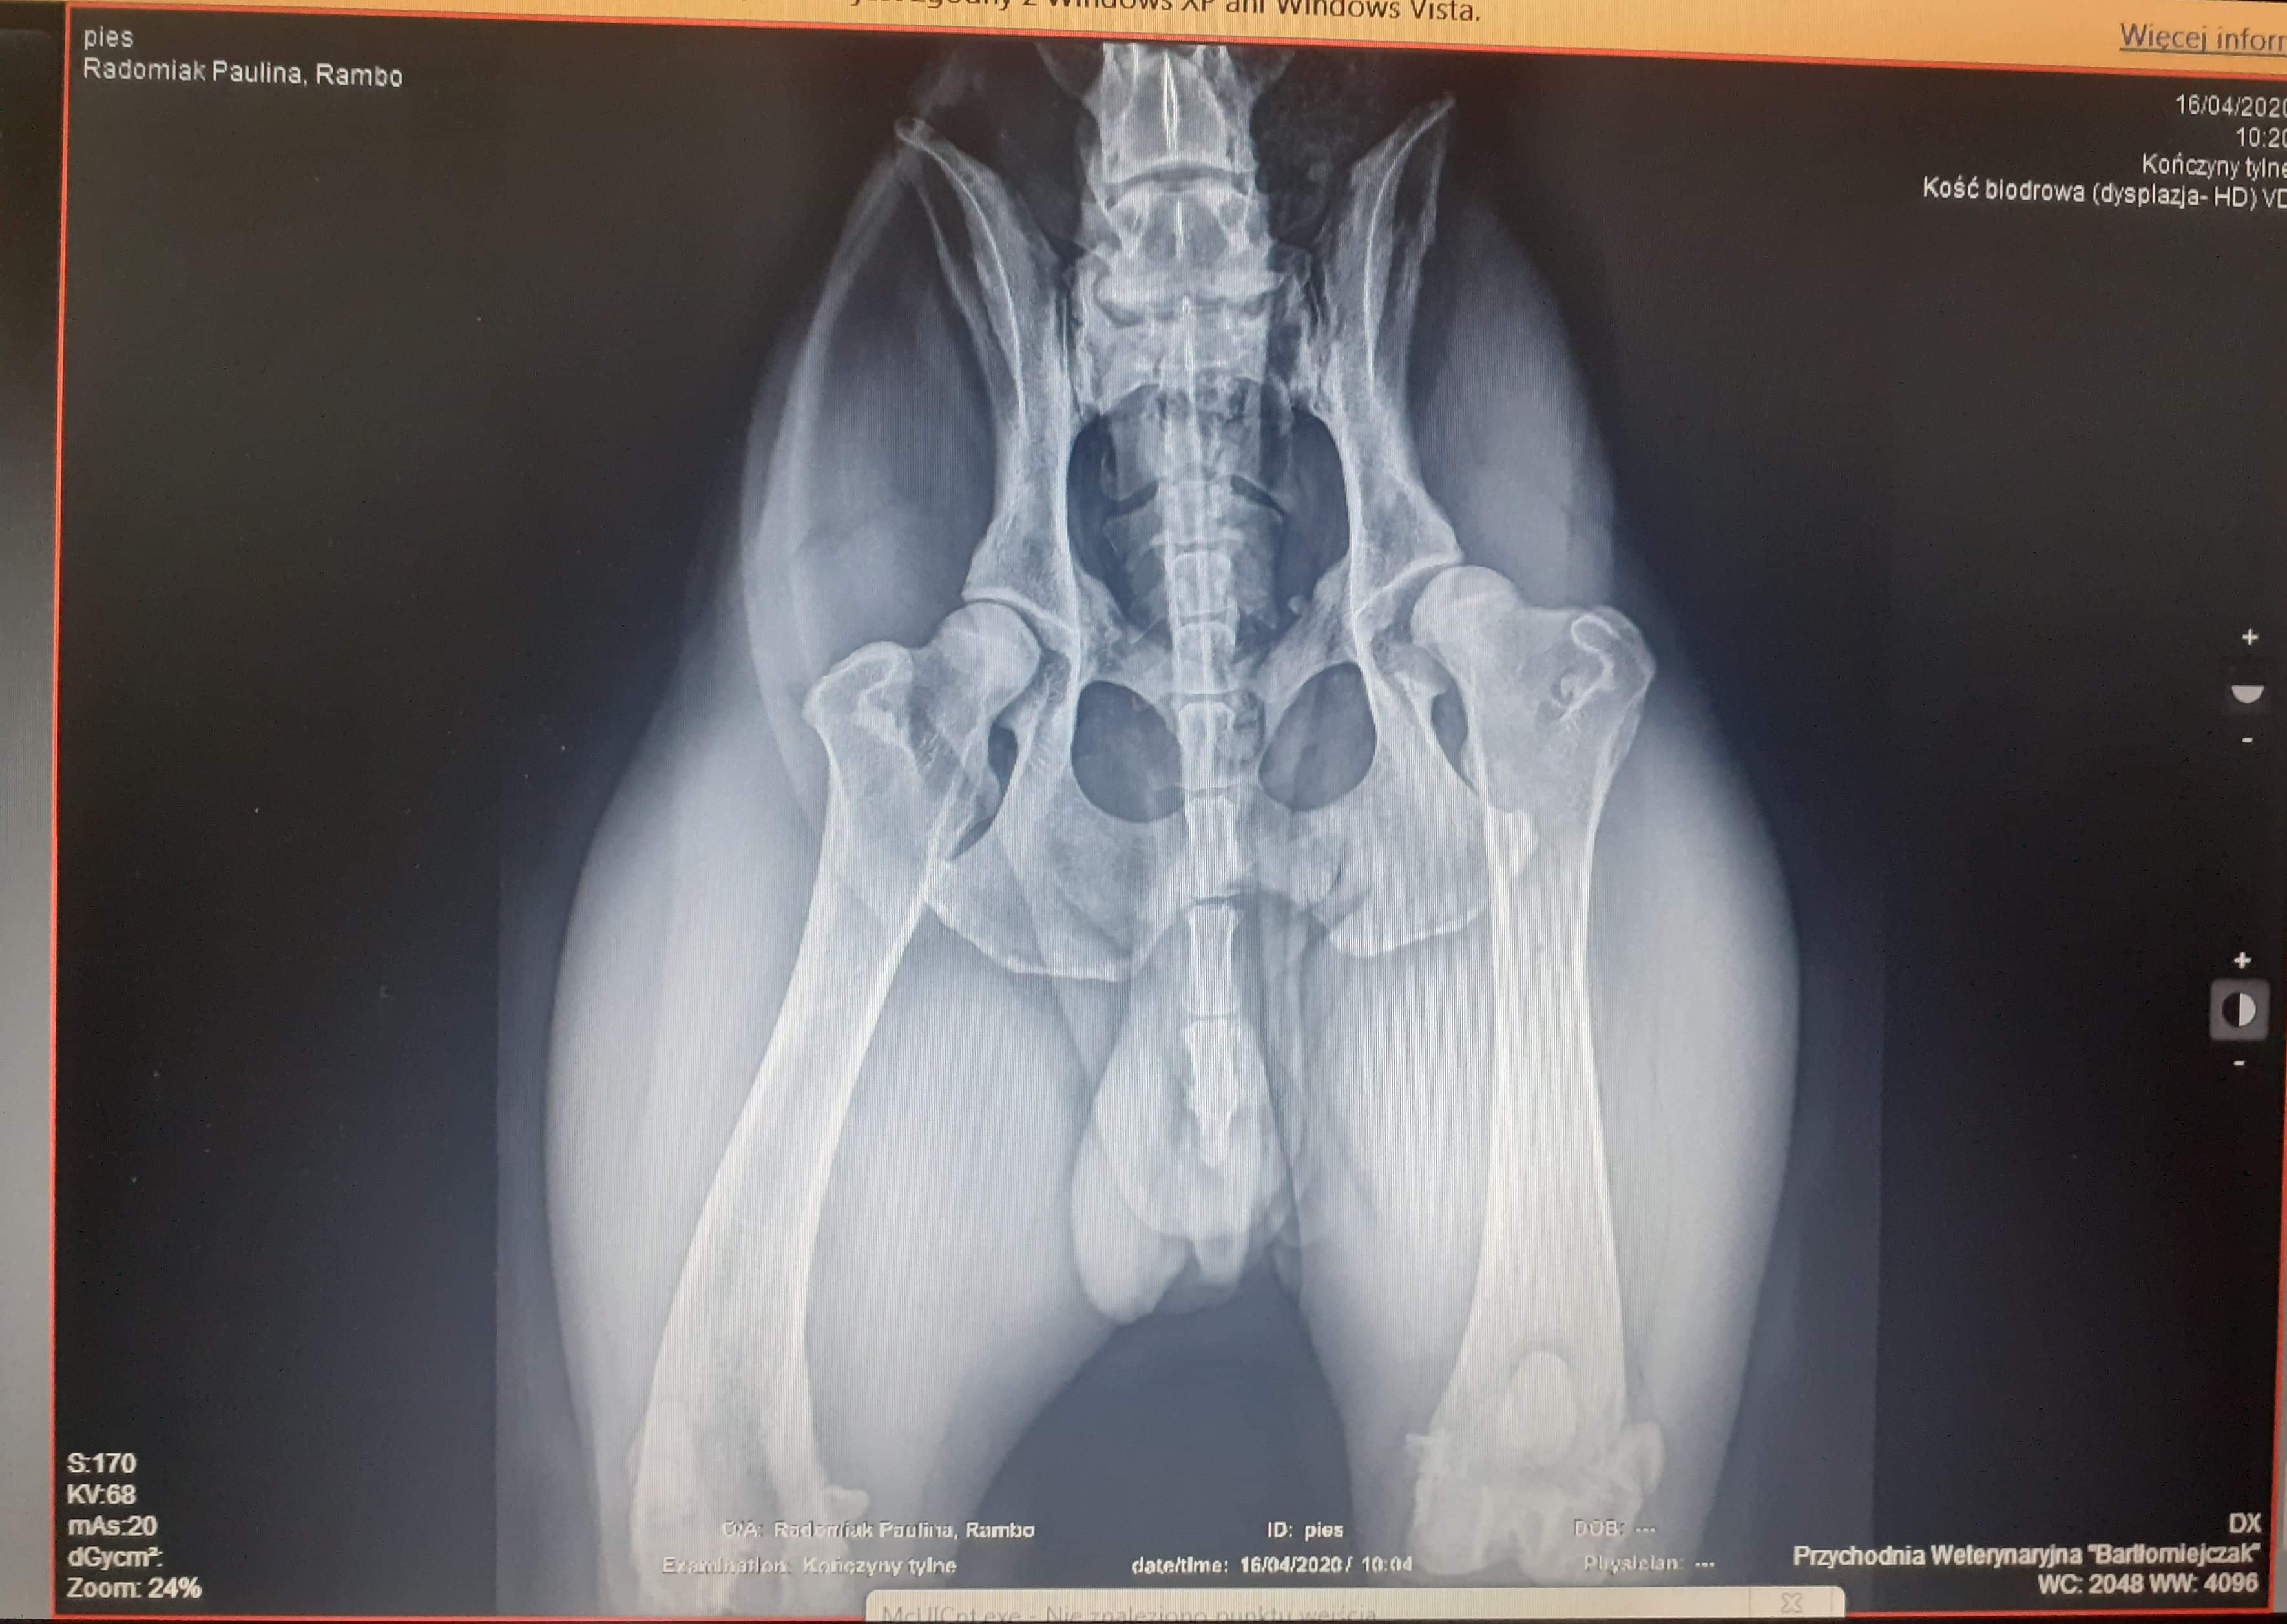

Zbieramy pieniądze na operację psa rasy Cane Corso. Wabi się RAMBO. Urodził się 1 stycznia 2018r, od jakiegoś czasu zmaga się z problemami stawów. Po zrobieniu licznych badań jedynym wyjściem okazała się operacja.. Rambo cierpi na dysplacje kości biodrowej kończyny tylnej.

Leczenie operacyjne

Potrójna osteotomia miednicy (TPO)

Operacja, której celem jest zapobieganie kalectwa.